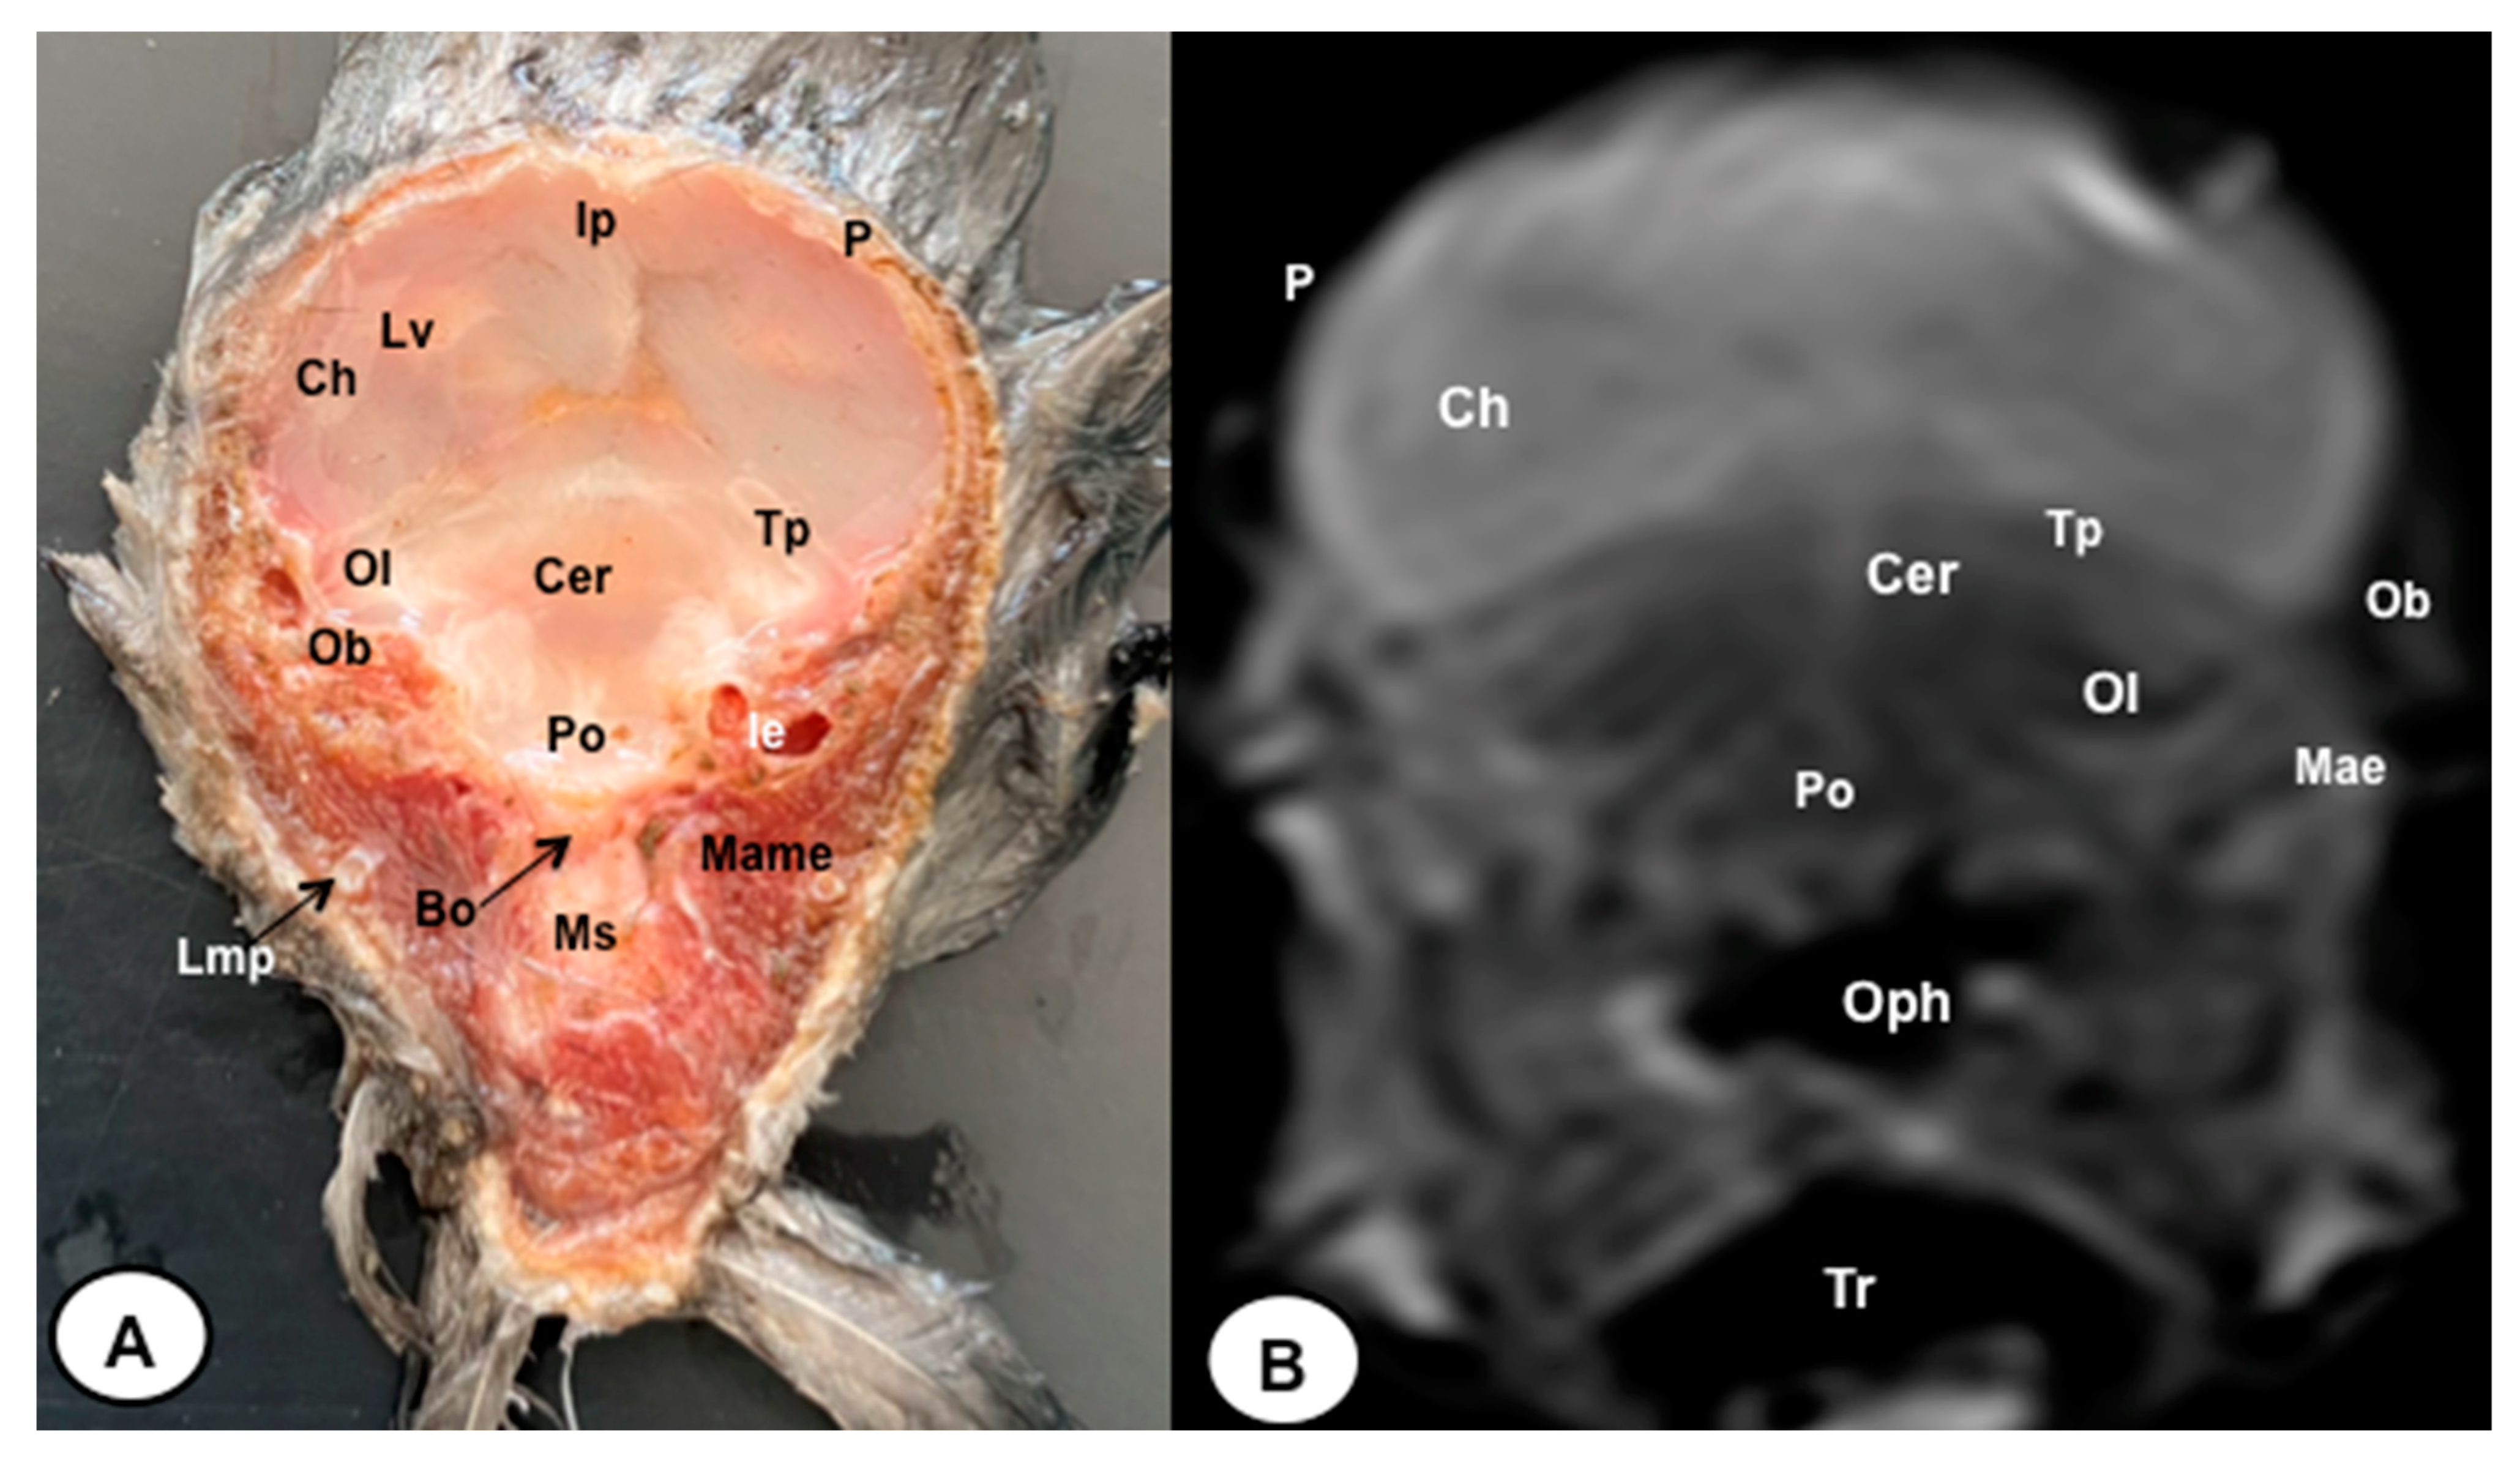

3.1. Anatomical Sections

3.2. Magnetic Resonance Imaging (MRI)